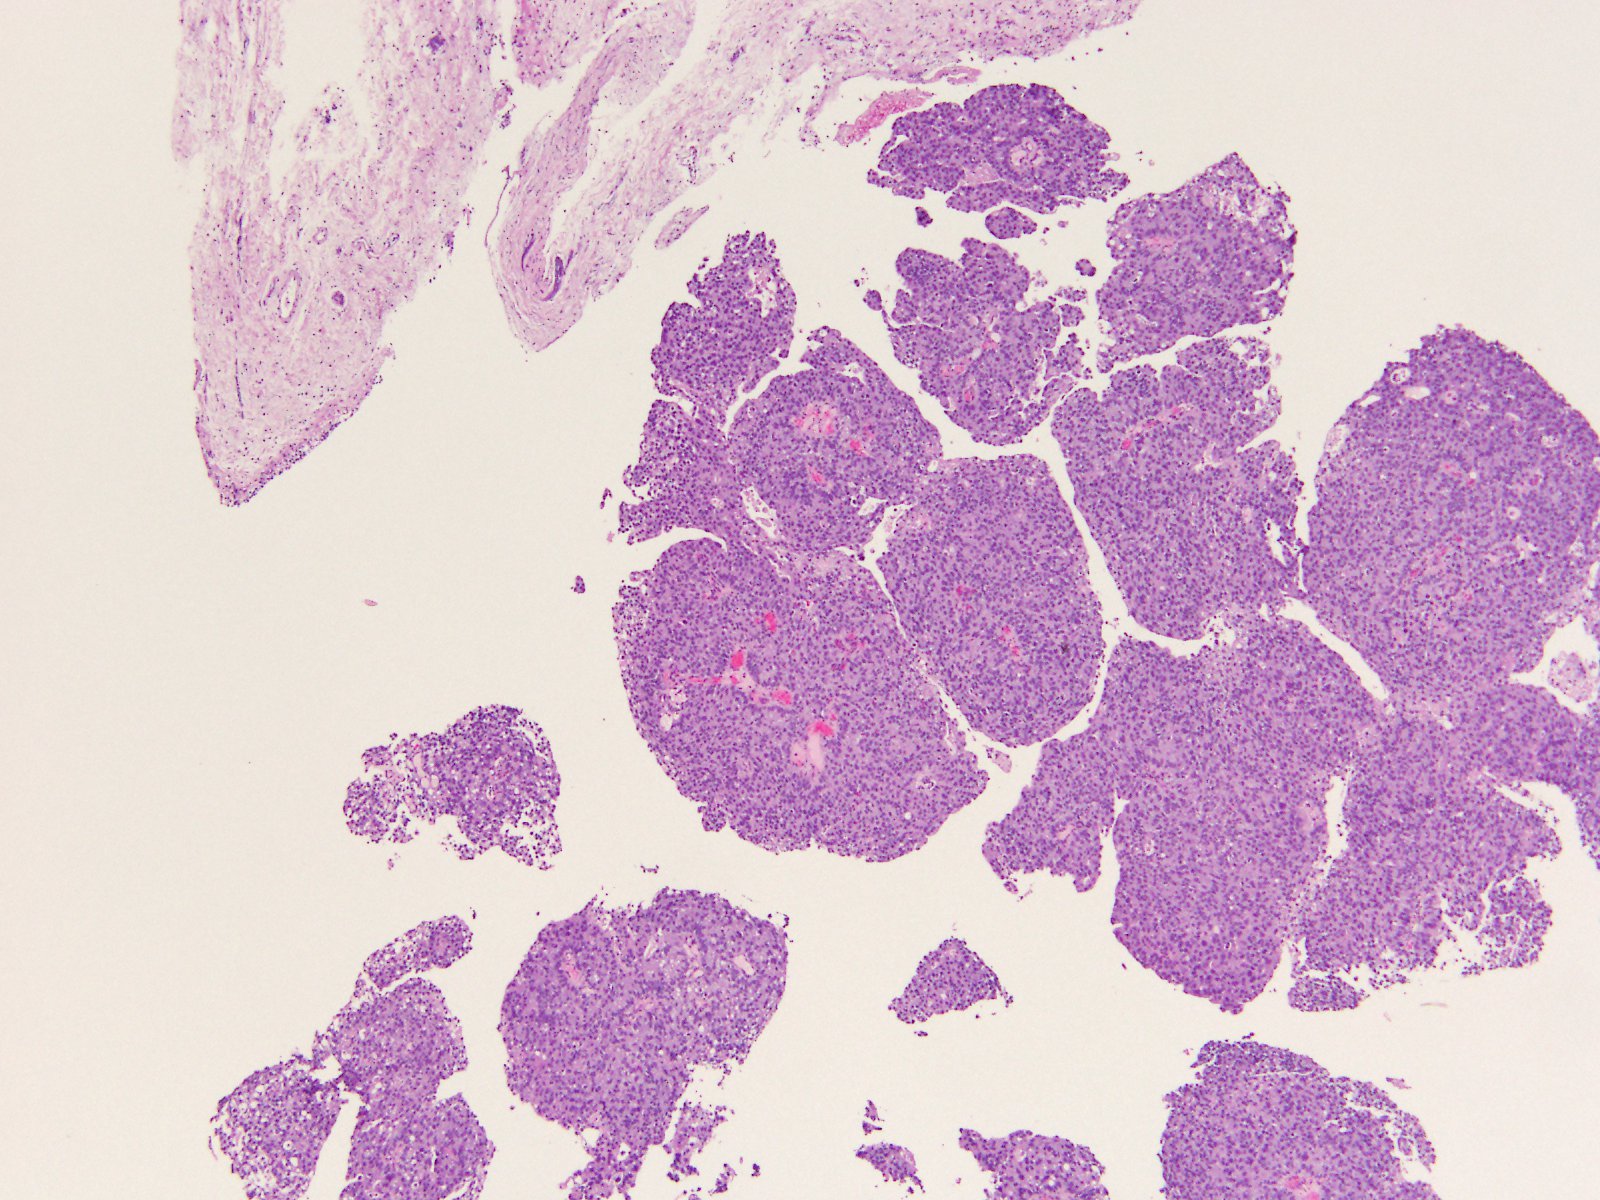

Bladder Papillary Lesions

Case ID: 565